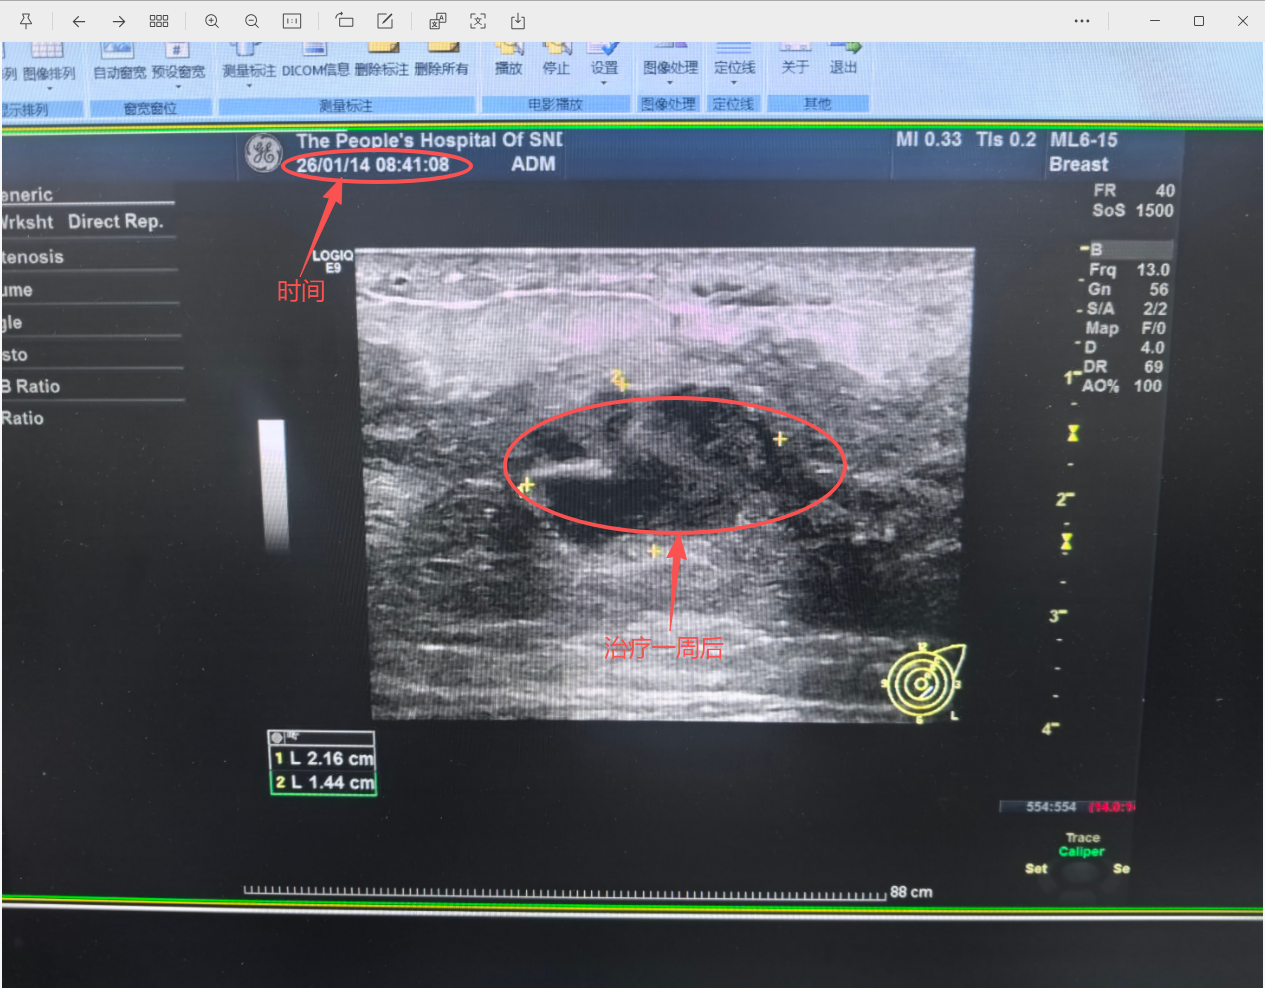

治疗一周后